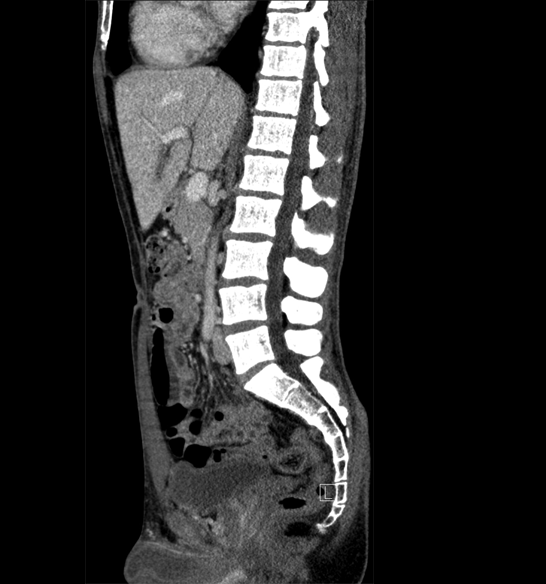

Body

Covers abdominal CT anatomy.